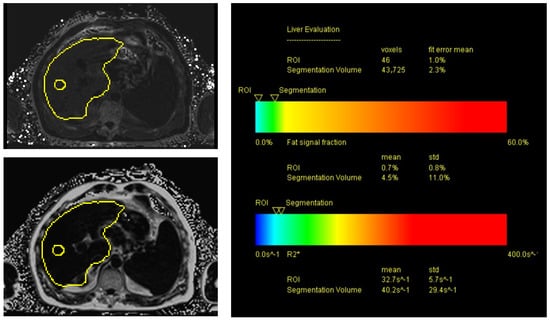

2.6. MRI of the Liver Using Proton Density Fat Fraction (PDFF) Sequences